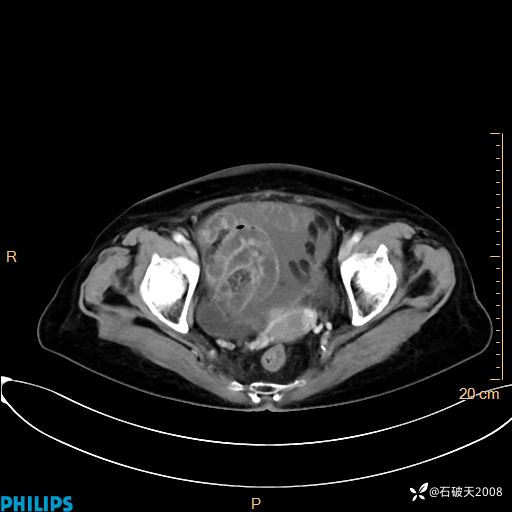

平扫